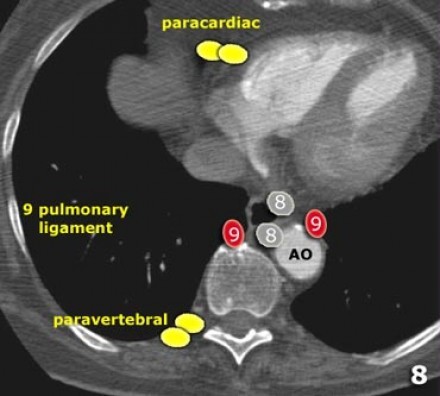

9. Linfonodos do ligamento Pulmonar

Linfonodos do ligamento pulmonar estão dentro do ligamento pulmonar, incluindo aqueles na parede posterior e inferior da veia pulmonar inferior.

O ligamento pulmonar é a extensão inferior das reflexões da pleura mediastinal que cercam o hilos.